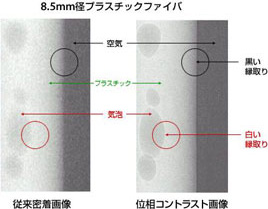

fig4 位相コントラスト画像とは

この位相コントラスト画像は、従来の通常X線撮影画像と比べるとシャープさ(鮮鋭性)が向上していることが分かります(fig4)。空気との境目に黒い筋が見え、チューブの中の気泡の辺縁が白く明確(シャープ)になっています。